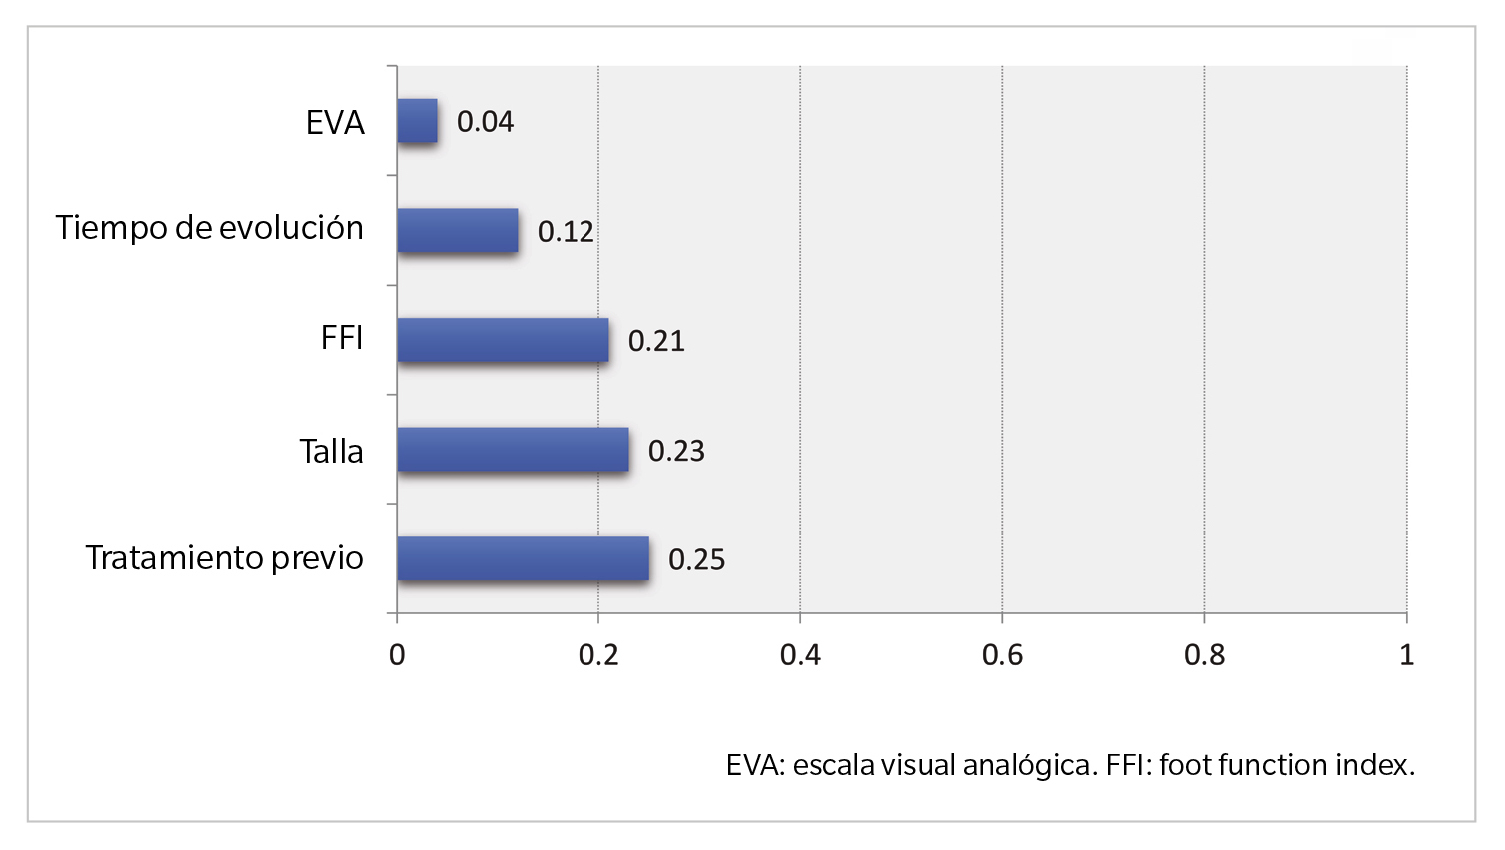

En el análisis de regresión lineal múltiple, se obtuvo un coeficiente de determinación R2 = 0.517, lo que indica que el modelo explica el 51.7 % de la variabilidad del grosor de la fascia plantar. Los predictores con significancia estadística para un mayor grosor de la fascia plantar fueron, de mayor a menor importancia relativa: haber recibido tratamiento previo (0.25), la talla del paciente en centímetros (0.23), el índice de función del pie medido con la escala FFI (0.21), el tiempo de evolución de la patología en meses (0.12) y, en menor medida, el dolor percibido según la escala EVA (0.04).

El resto de las variables analizadas no mostraron significancia estadística en este modelo. Estos hallazgos resaltan la influencia combinada de factores clínicos y antropométricos en la variabilidad del grosor fascial. Específicamente, el antecedente de tratamiento previo y la talla del paciente emergen como los predictores más relevantes, mientras que el dolor percibido muestra una influencia limitada (Figura 4).

Figura 4. Importancia del predictor.

El objetivo principal de este estudio fue analizar los factores que influyen en el grosor de la fascia plantar en pacientes con fasciopatía, evaluando específicamente el impacto de variables clínicas y antropométricas como el tratamiento previo, la talla, el FFI, el tiempo de evolución, el dolor medido con la escala EVA, la masa corporal y la biconvexidad de la fascia plantar. Los resultados principales muestran que el grosor de la fascia plantar está significativamente asociado con el antecedente de haber recibido tratamiento previo y la talla del paciente, seguidos por el FFI y el tiempo de evolución.

Los factores pronósticos en la FP se analizan con frecuencia para proporcionar información sobre la medida en que los pacientes se beneficiarán de las diferentes modalidades de tratamiento. El engrosamiento de la fascia plantar es de particular interés, ya que es una manifestación prominente y frecuente de la FP y se puede evaluar cuantitativamente. En este estudio descriptivo, el grosor medio de la fascia plantar en hombres con FP fue de 5.97 ± 1.08 mm, y los predictores significativos de un mayor grosor fascial incluyeron no haberse realizado tratamiento previo, una baja talla, una alta puntuación en la escala FFI y un corto tiempo de evolución de la enfermedad.

En conclusión, en el presente estudio se identificaron los principales factores asociados al grosor de la fascia plantar en pacientes varones con FP. Los resultados muestran que el antecedente de tratamiento previo y la talla son los predictores más relevantes, seguidos por el FFI y el tiempo de evolución, mientras que el dolor percibido según la escala EVA y otras variables como la masa corporal y la biconvexidad tuvieron una influencia limitada. Estos hallazgos subrayan la importancia de considerar factores clínicos y antropométricos para comprender las variaciones en el grosor de la fascia plantar y orientar intervenciones diagnósticas y terapéuticas. Además, los datos obtenidos refuerzan la utilidad de combinar herramientas clínicas y ecográficas para valorar el impacto de diferentes variables en esta condición. Futuras investigaciones deberían enfocarse en validar estos resultados en cohortes más amplias y en explorar intervenciones específicas para optimizar los resultados clínicos en pacientes con FP.